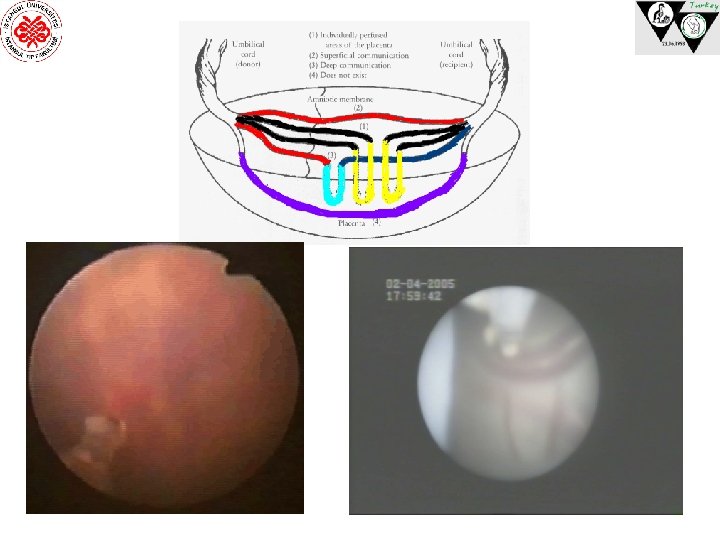

TTTS AA En sık ve yüzeyel VV Daha az ve yüzeyel AV/VA Daha az ama derinde AA ile AV veya VA arasındaki dengenin bozulması

TTTS’da TEDAVİ 1. Medikal Tedavi (İndomethasin) Kontraendike (vericide renal akım azalması) 2. Amniyoredüksiyon 3. Amniyotik Septostomi ve Amniyoredüksiyon 4. Plasental Cerrahi a) Plasenta yüzey damarlarının lazer ile koagülasyonu (selektif/nonselektif) b) Bipolar kordon koagülasyonu

TRAP’de TEDAVİ KORDON LİGASYONU LASERLE KOAGÜLASYON Video BİPOLAR ELEKTROKOAGÜLASYON